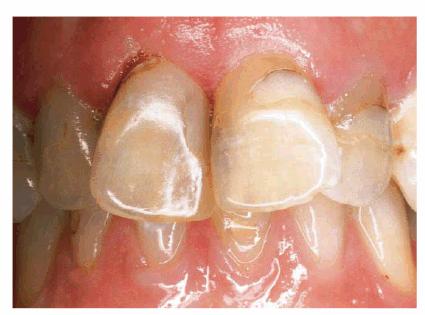

PROBLEM: This 58-year-old housewife was concerned about her eroded,

crowded, and stained front teeth (Figures 24-5A, and 24-5B). Measurement with a dental dial

caliper helped to accurately determine available space for reproportioning tooth

size (Figure 24-5C). Although orthodontics was

mentioned as a first step to an ideal solution, the patient preferred to accept

a compromise treatment of porcelain laminates and cosmetic contouring. Although

crowding was less of a concern to the patient (Figures 24-5D, and 24-5E), she nevertheless decided to have

straighter-looking teeth through a compromise treatment of porcelain laminates

that would also esthetically correct the erosion and discoloration.

Figure 24-5A: This 58-year-old woman was dissatisfied with her crowded, eroded, and discolored teeth.

Figure 24-5B: Preoperative view.